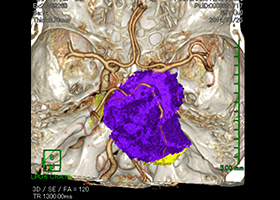

① 髄膜腫(特に頭蓋底部)

髄膜腫は脳を覆っている硬膜という組織から発生する良性腫瘍です。脳表にできたものは摘出が容易ですが、脳深部(特に頭蓋底部)にできたものは脳実質や神経、血管を巻き込みながら腫瘍が存在しているので摘出は困難です。当科では術中ナビゲーションシステムや神経生理学的モニタリングを使用しながら安全かつ効率的な手術を行っています。

症例1)65歳男性、頭蓋底部巨大髄膜腫、外科手術のみ

[画像所見]

MRI造影検査で巨大脳腫瘍を認めます。

-

造影3DCT検査:錐体斜台部巨大髄膜腫認め

神経や血管を巻き込んでいます。 -

術前手術シュミレーション

術前 -

術後腫瘍は全摘出されました。